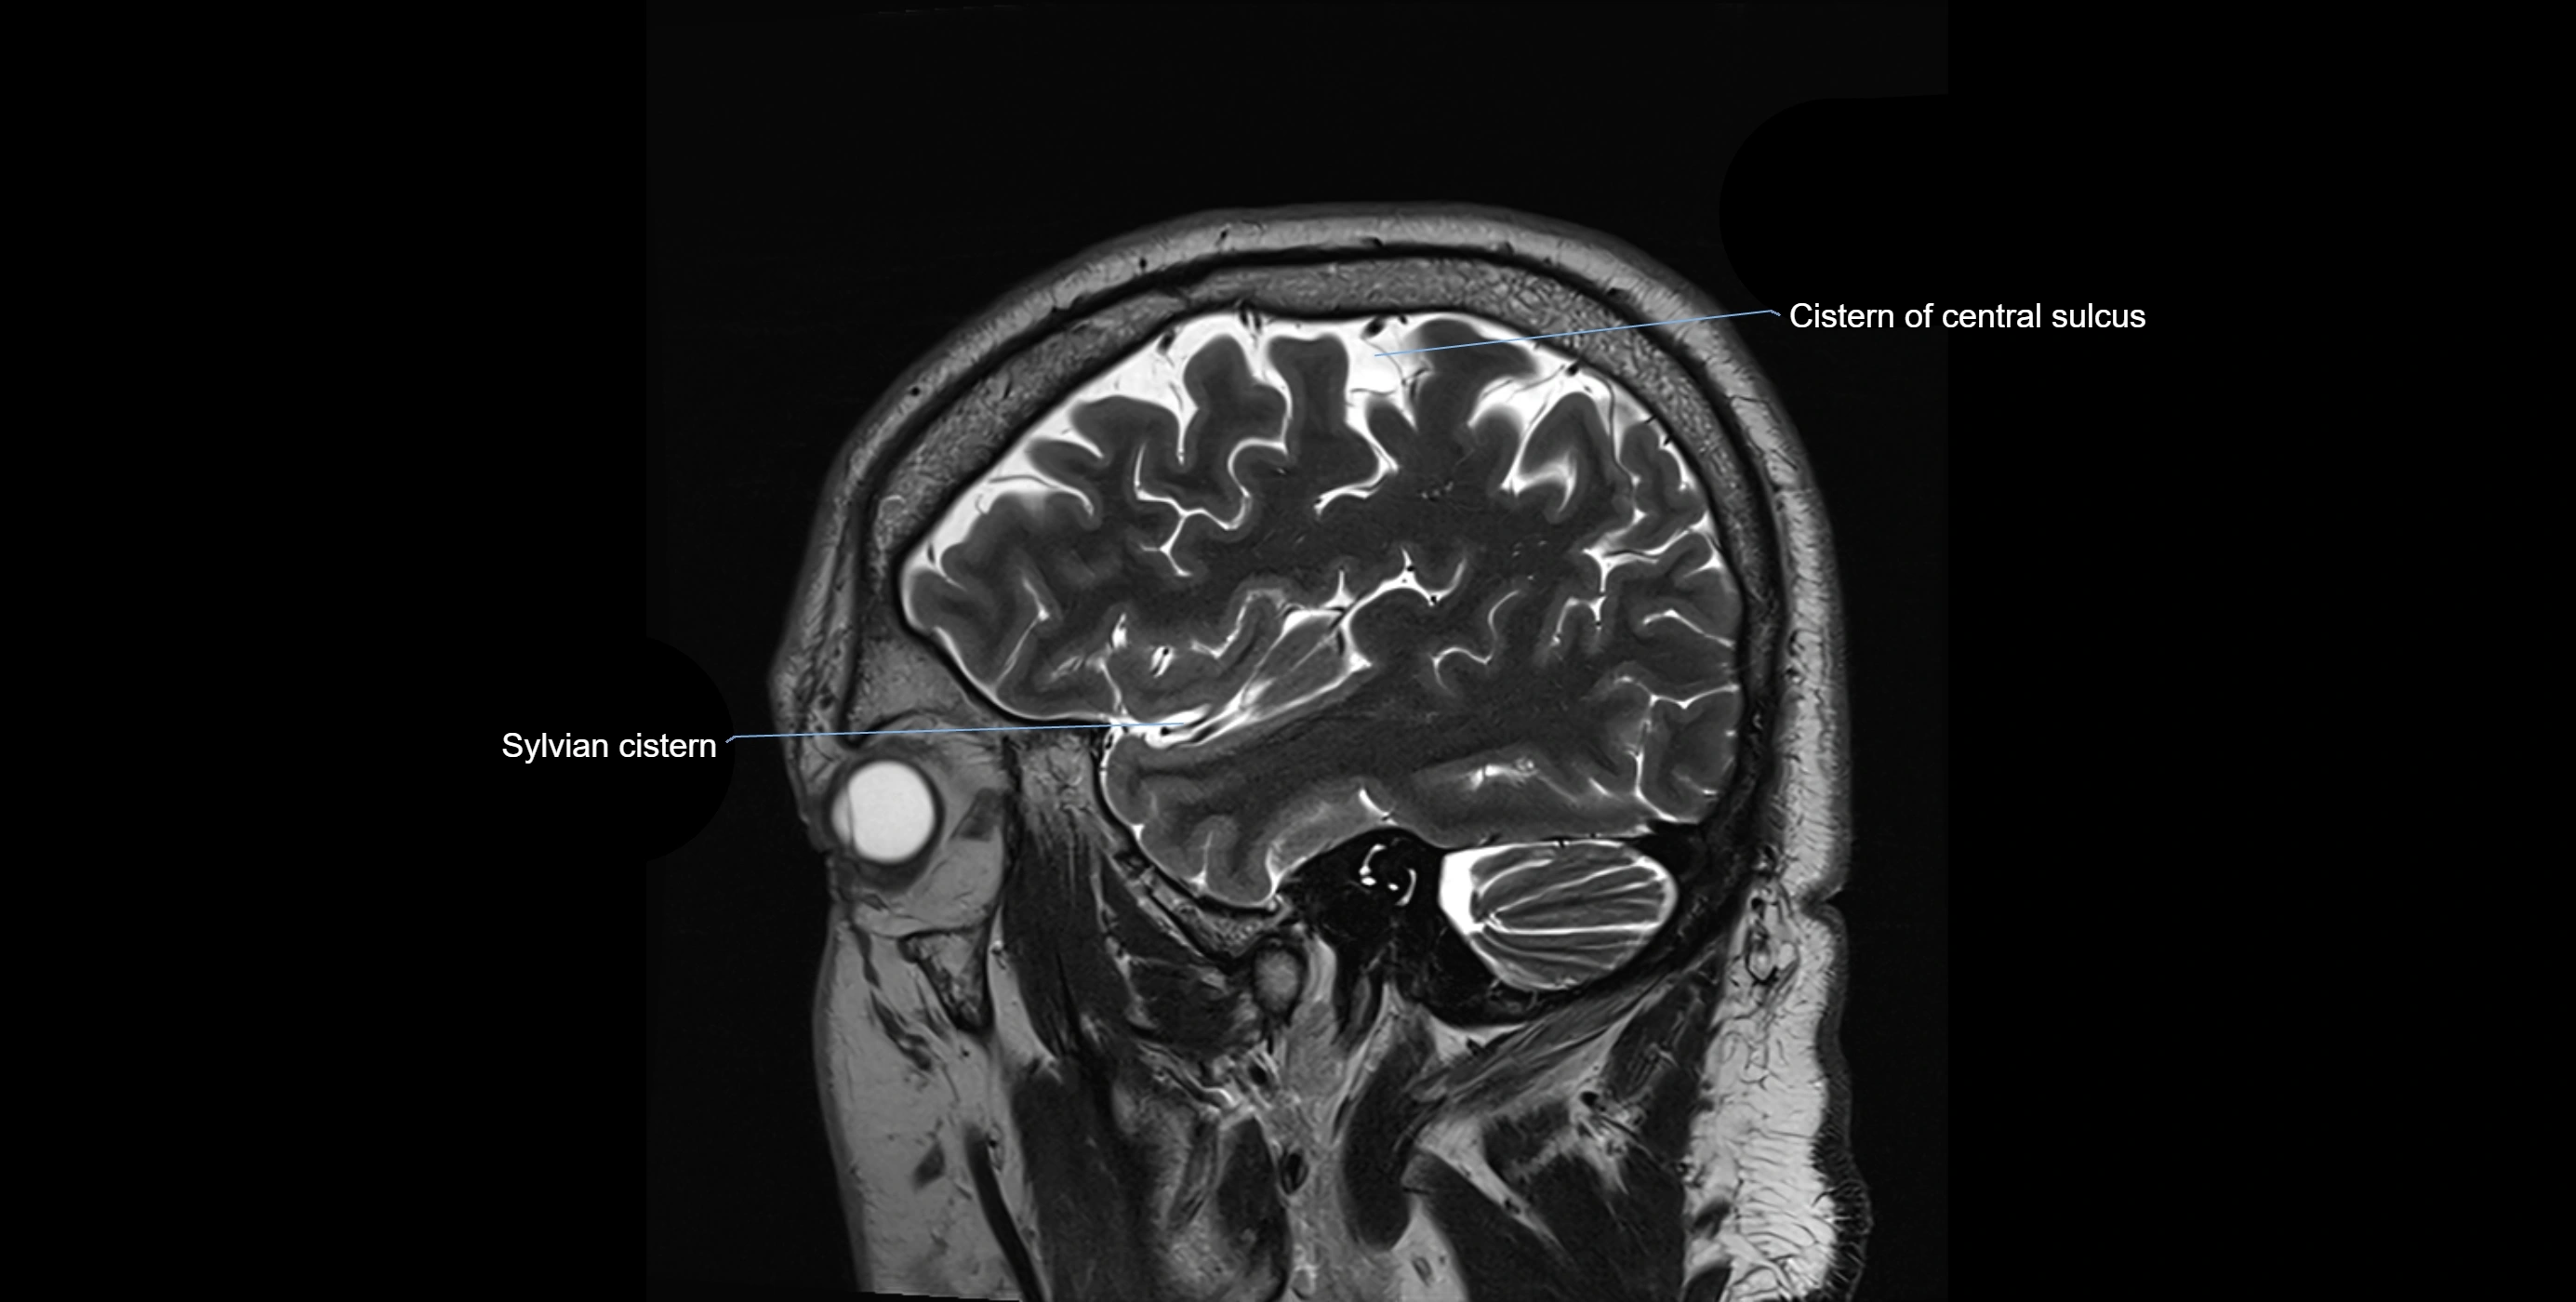

CT image

image